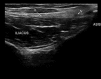

Neuromuscular ultrasound (NMUS) is becoming a standard element in the evaluation of peripheral nerve and muscle disease. When obtained simultaneously to electrodiagnostic studies, it provides dynamic, structural information that can refine a diagnosis or identify a structural etiology. NMUS can improve patient care for those with mononeuropathies, polyneuropathy, motor neuron disease and muscle disorders. In this article, we present a practical guide to the basics of NMUS and its clinical application. Basic ultrasound physics, scanning techniques and clinical applications are reviewed, along with current challenges.